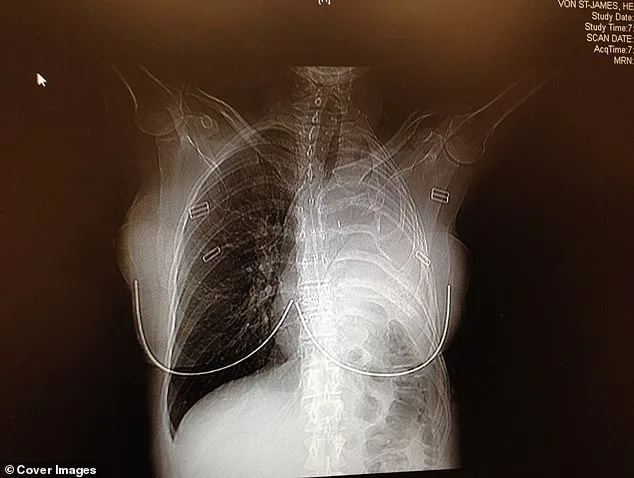

In February 2006, doctors removed her left lung, the rib above it, the lining of her heart, and part of her diaphragm. In their place, they used surgical Gore-Tex—the same material used in waterproof clothing—to rebuild parts of her chest. The surgery was a success. Surgeons had excised the tumor with perfect margins, leaving no visible cancer behind. As a precaution, doctors infused warm drugs directly into her chest cavity, rocking her back and forth for an hour to circulate the medicine and kill any remaining cancer cells. "Patients call it the 'shake and bake,'" Von St James said. She endured four rounds of chemotherapy and 30 sessions of radiation. "People say once you survive cancer, everything should be great," she said. "But there are a lot of ongoing physical things that happen after surgeries."